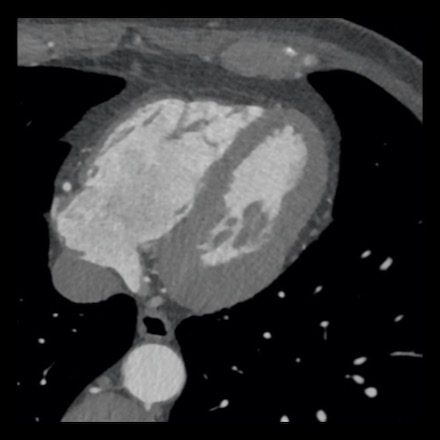

case 4 – CAD-RADS 3/P1/I+ thrombus left ventricle

First, scroll through the CTA images.

How would you describe the findings on the coronary CTA?

The findings are:

- Moderate (50-69%)

stenosis in the proximal LAD caused by a non-calcified plaque. - Variant of

sinoatrial (SA) nodal artery. The artery usually arises from the RCA as a second

branch after the conus artery, however in this case it arises from the LCX,

courses behind the aorta, anastomosing with the right atrium and with a small

branch supplies the SA-node of the heart. - Thrombus in the

apex of the left ventricle. - CTP was performed

in this patient. CTP showed a perfusion defect at stress imaging in the

territory of the LAD (I+), at rest no perfusion defect was visible.

This patient classifies as CAD-RADS 3/P1/I+, which means

this patient requires further investigation.